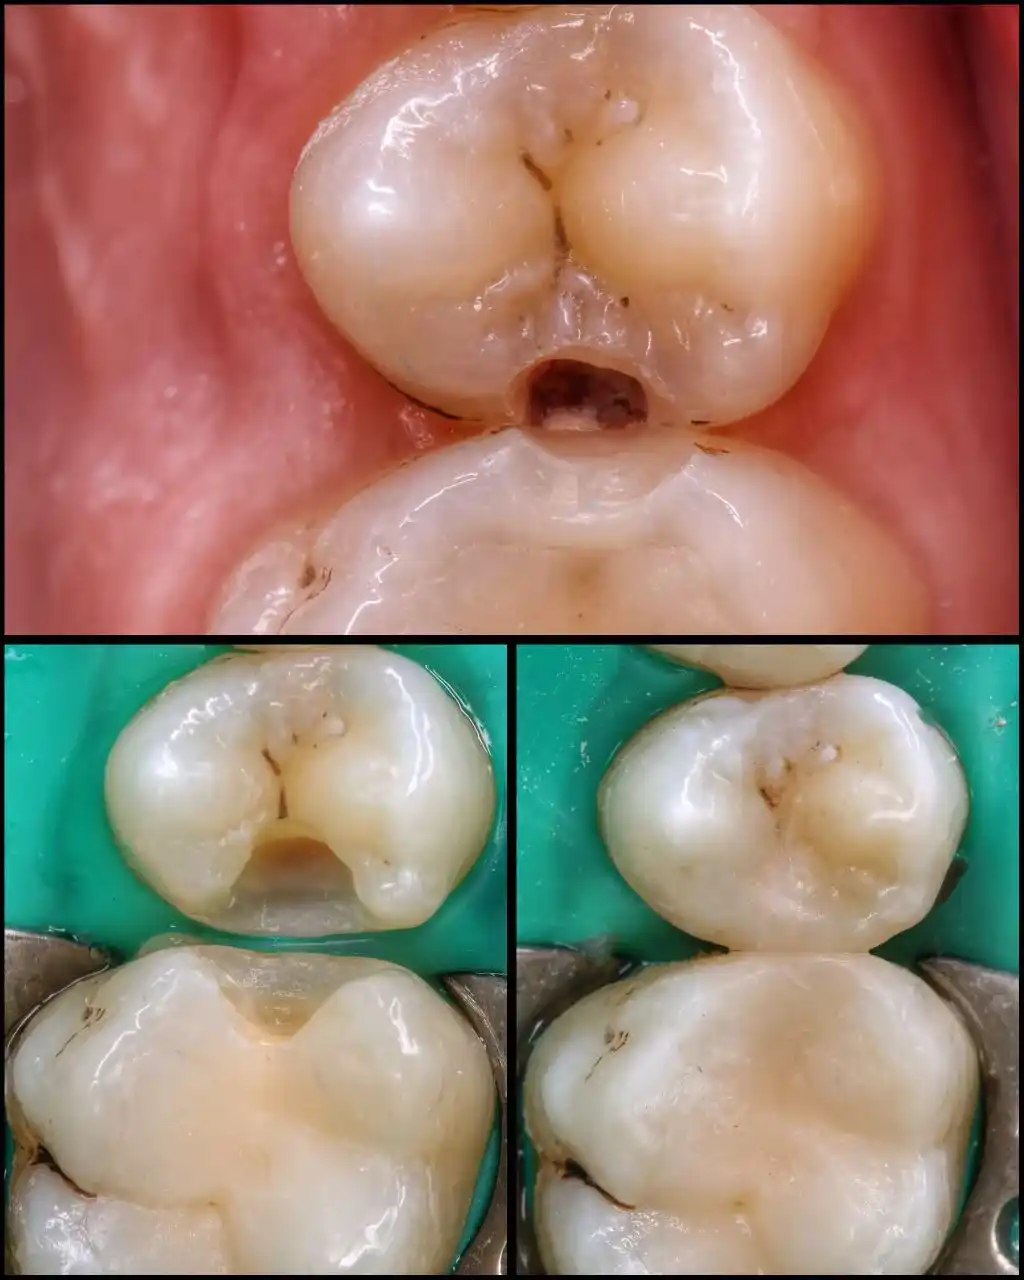

Наші роботи "лікування зубів вдома"

Лікування карієсу вдома.

Лікування зубів вдома при карієсі включає видалення пошкоджених тканин та встановлення фотополімерних пломб з ізоляцією зубів системою кофердам. Сучасні матеріали та портативне обладнання гарантують високу якість реставрації та довговічність результату. Усі процедури проходять із дотриманням суворих санітарних норм.

1) фотополімери Gradia (Японія) , Estelite sigma quick, Estelite Universal Flow (Японія) , Venus ( Німеччина )

2) адгезивна система Optibond FL, Kerr (золотий стандарт у стоматології) (США), а також Prime&Bond Universal компанії Dentsply Sirona ( США )